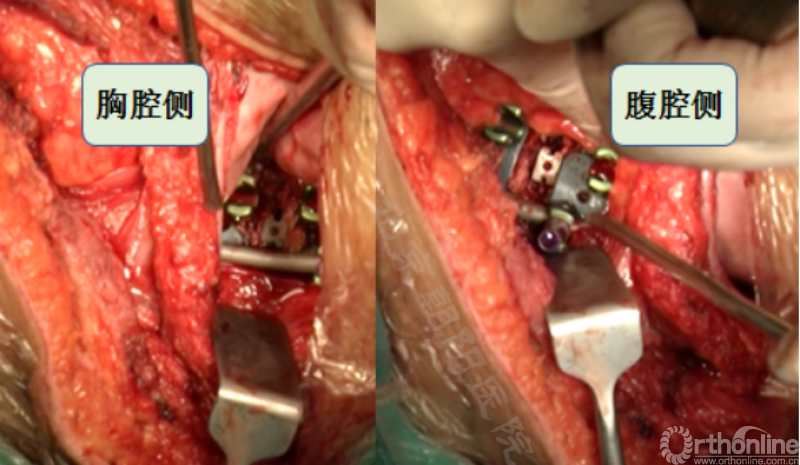

切开横膈进入胸腔侧,术中由双肺呼吸改为凹侧单肺呼吸。

沿脊柱表面纵行切开腹膜,显露腹腔侧,注意避免伤及节段性血管。

内固定选择的是5.5mm双棒系统,先置入顶椎的螺钉垫板。

置入顶椎的椎体螺钉,螺钉可置入椎体中部到后方1/3之间的范围内。

使用双棒系统时,先置入背侧的螺钉,螺钉指向椎体中线,后置入腹侧的螺钉,螺钉轻度指向后侧。形成对椎体的三角形抓持力。

胸腔侧、腹腔侧螺钉全部置入后,骨移植物植人的越靠近后纵韧带或者纤维环的后缘越好。